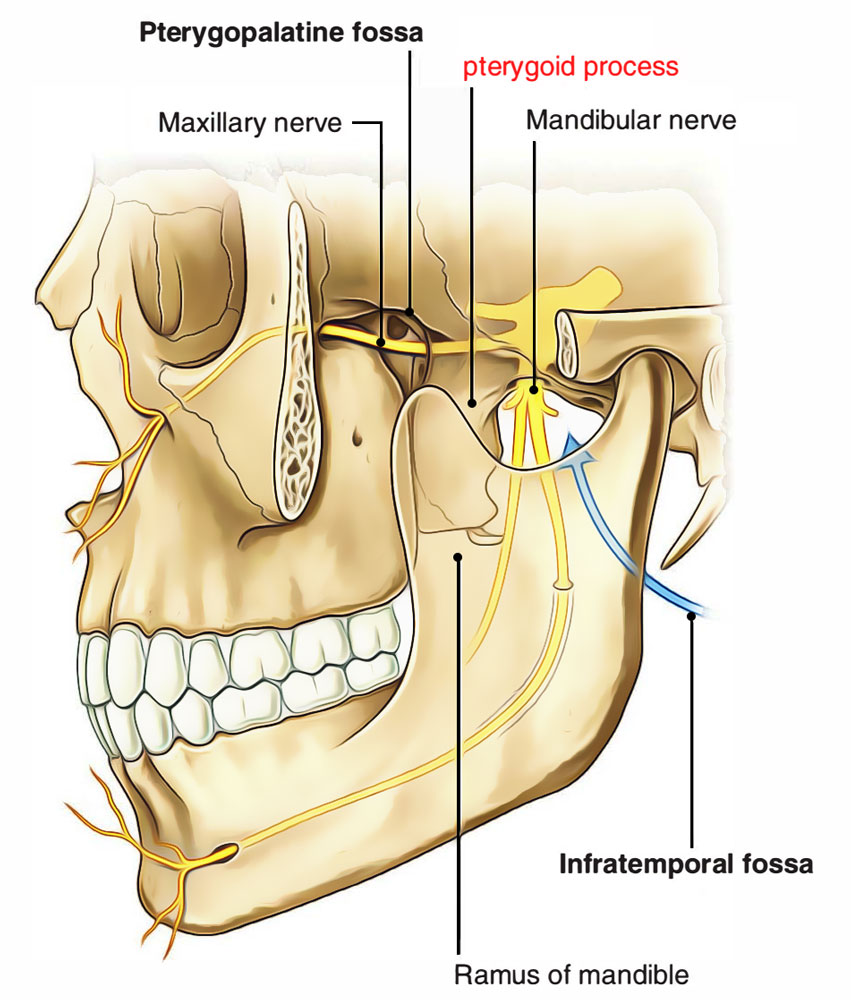

Анатомические особенности: фотографии ямок черепа, височной и подвисочной крылонебной